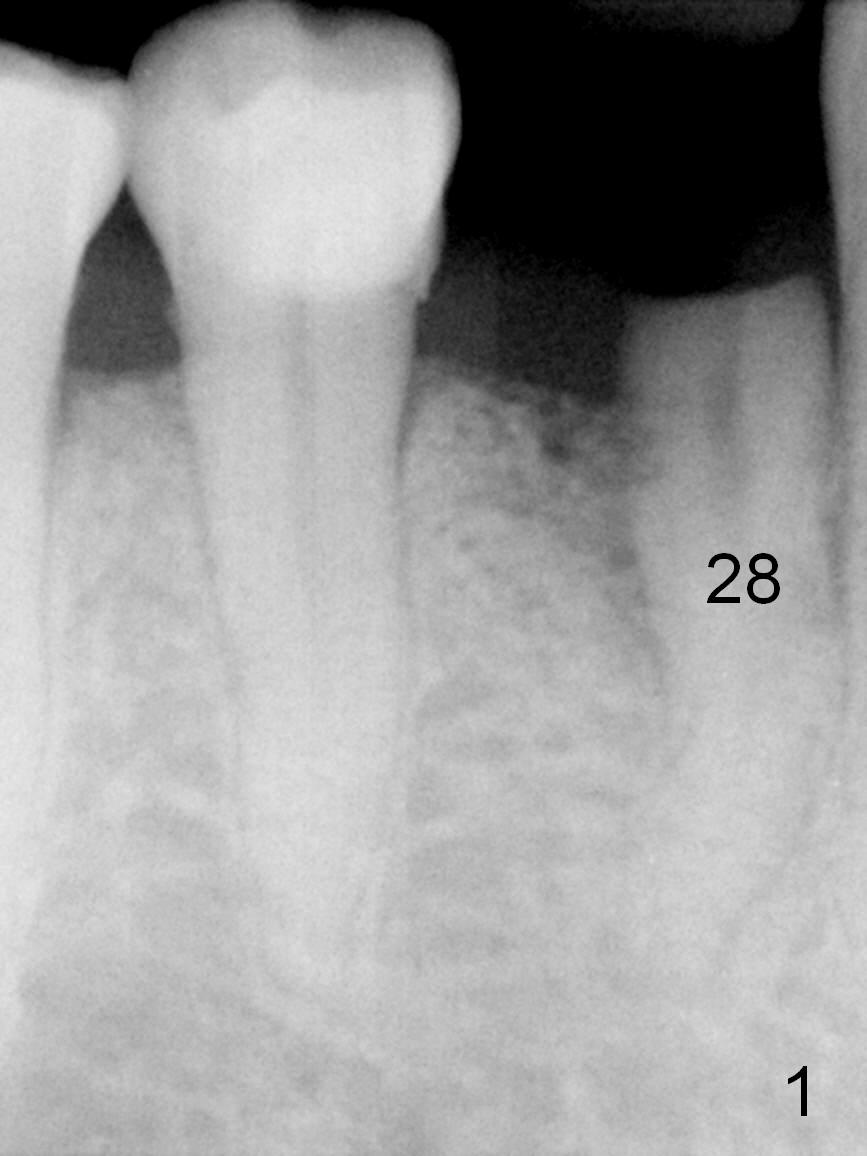

A 73-year-old man requests extraction of the lower right 1st premolar and implant restoration (Fig.1: #28). The root of the affected tooth (Fig.2 black area) is not only curved, but also deviated mesially (close to the root of the canine (blue dashed line). Osteotomy should be established with a sharp 1.5 mm pilot drill obliquely in the distolingual slope of the socket (treated with Metronidazole, Fig.3 (green line)). Once bony penetration is obtained, the drill straightens up in the middle of the socket and along the ideal long axis (Fig.4). Remove the bone in between (Fig.4 pink dashed line) if there is resistance to change in the trajectory. A PA is taken to confirm the position and trajectory. Then extend the osteotomy (Fig.5 green line) , but not beyond the apices of the neighboring tooth and the original socket (brown line), since the Mental Loop is nearby (Fig.2-5 red dashed line).